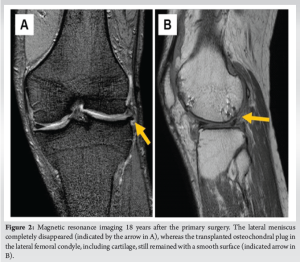

A physical examination conducted 18 years after OAT revealed a slight swelling in the left knee and tenderness of the medial joint space. The left knee had a reduced range of motion (ROM) of 0°–110°, whereas the right knee had a ROM of 0°–150°. However, no joint instability was detected. Magnetic resonance imaging (MRI) showed a cartilage defect in the medial femoral condyle (MFC) and disappearance of the LM, but the transplanted osteochondral plug in the LFC still remained (Fig. 2).